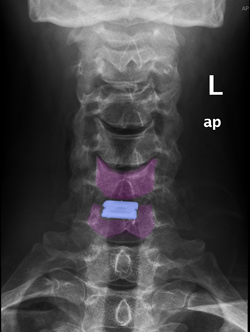

Πρόσθια αυχενική δισκεκτομή και τοποθέτηση τεχνητού αυχενικού δίσκου (μπλέ) Α6-Α7. |

Πρόσθια αυχενική δισκεκτομή και τοποθέτηση τεχνητού αυχενικού δίσκου (μπλέ) Α6-Α7. Ακτινογραφίες με τον αυχένα σε ουδέτερη θέση (αριστερά), έκταση (κέντρο) και κάμψη (δεξιά). Αναδεικνύεται η κίνηση στο χειρουργημένο μεσοσπονδύλιο διάστημα. |